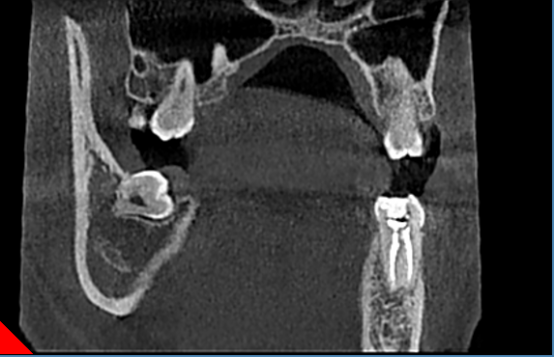

1.提供各种颌面信息及三维图像信息,精确地获得所需术前诊断信息。

2.为种植提供测量颌骨宽度、长度、密度及各种距离、角度等综合信息,以选择各种种植体尺寸及位置。

3.重要结构的定位,种植体间距离安全碰撞检测(神经管、上颌窦、病变位置等)避免手术中发生突发情况。

4.真实模拟种植体的位置,可选择任意种植型号、大小尺寸等,方便医患直观交流讨论。

5.定制手术外科导板,精确定位种植体位置及方向,提供微创及即刻种植方案